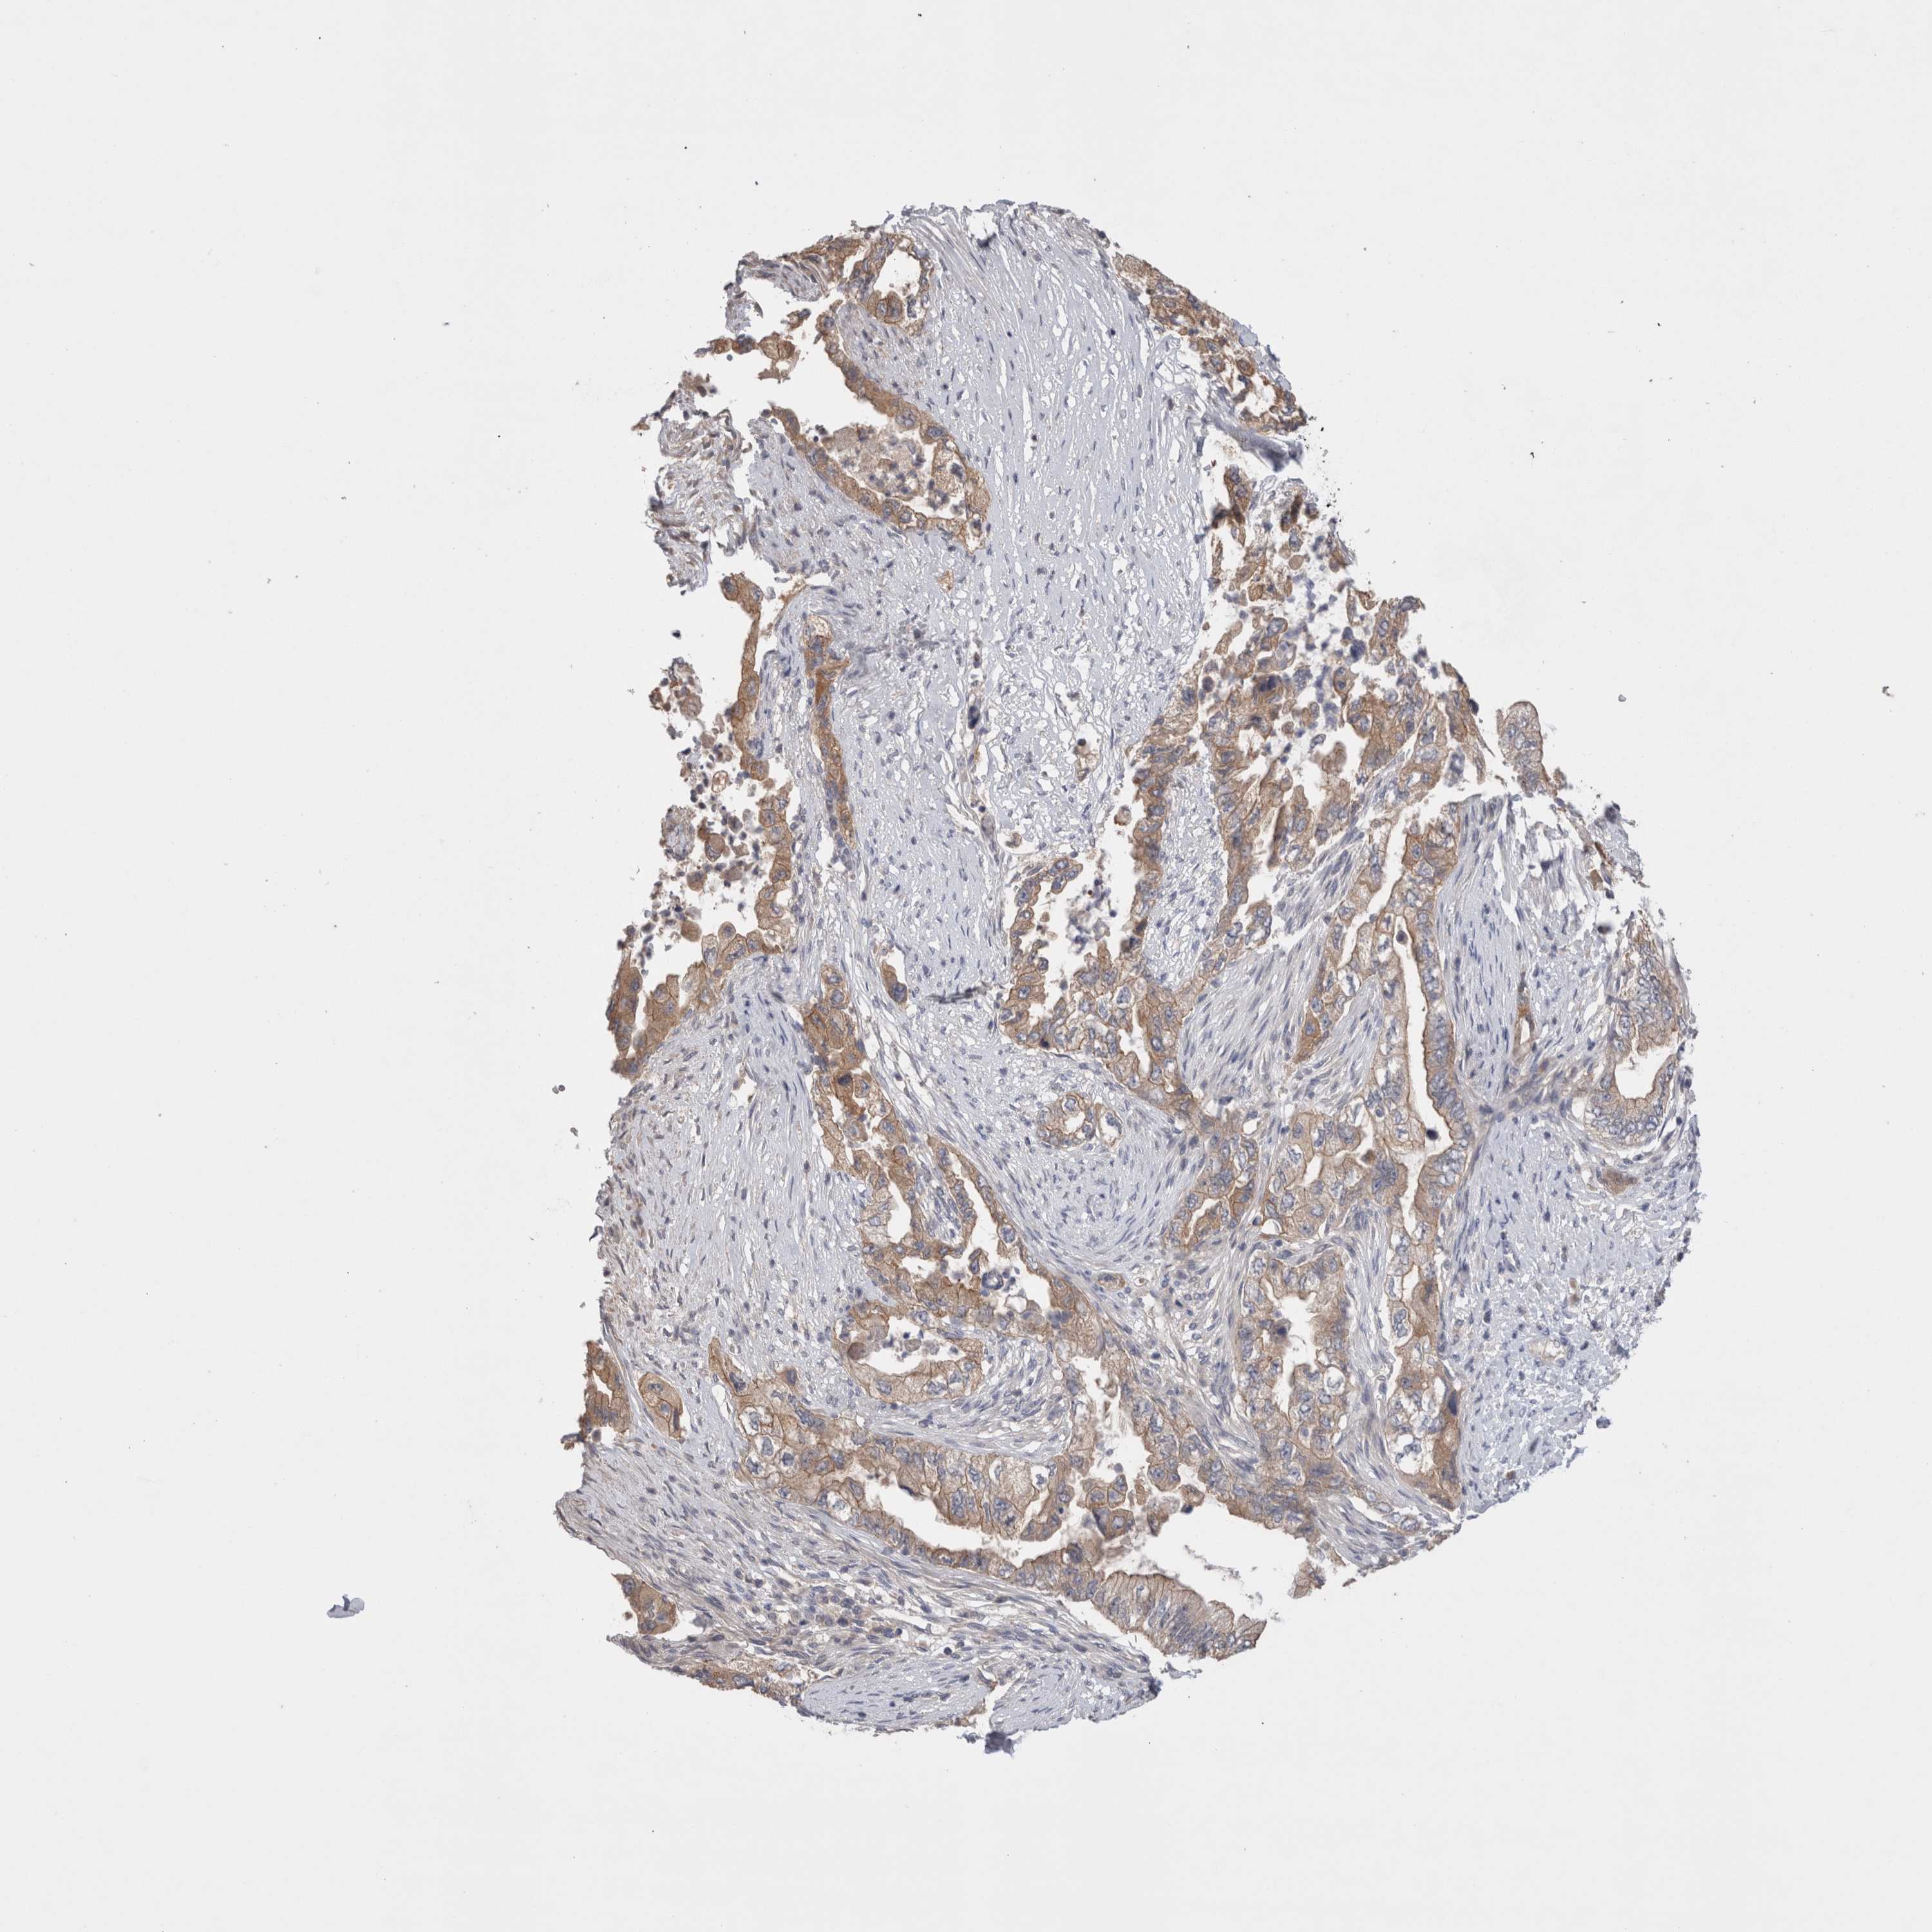

PANCREATIC CANCER - Protein expressioni

A mouse-over function shows sample information and annotation data. Click on an image to view it in a full screen mode. Samples can be filtered based on level of antibody staining by selecting one or several of the following categories: high, medium, low and not detected. The assay and annotation is described here.

Note that samples used for immunohistochemistry by the Human Protein Atlas do not correspond to samples in the TCGA dataset.

Antibody stainingi

Antibody staining in the annotated cell types in the current human tissue is reported as not detected, low, medium, or high, based on conventional immunohistochemistry profiling in selected tissues. This score is based on the combination of the staining intensity and fraction of stained cells.

Each image is clickable and will lead to virtual microscopy that enables deeper exploration of all samples and also displays staining intensity scores, fraction scores and subcellular localization as well as patient and tissue information for each sample.

Antibody HPA024335

Staining

High

Medium

Low

Not detected

Intensity

Strong

Moderate

Weak

Negative

Quantity

>75%

75%-25%

<25%

None

Location

Nuclear

Cytoplasmic/membranous

Cytoplasmic/membranous,nuclear

Adenocarcinoma, NOS